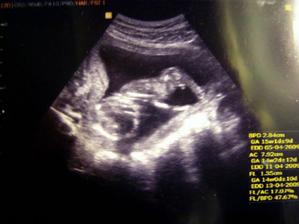

27.11..tak velky UZ 21+0ttt dopadl dobre Oliver je zdrav a ma vse co ma mit.....vazi 404g 🙂)